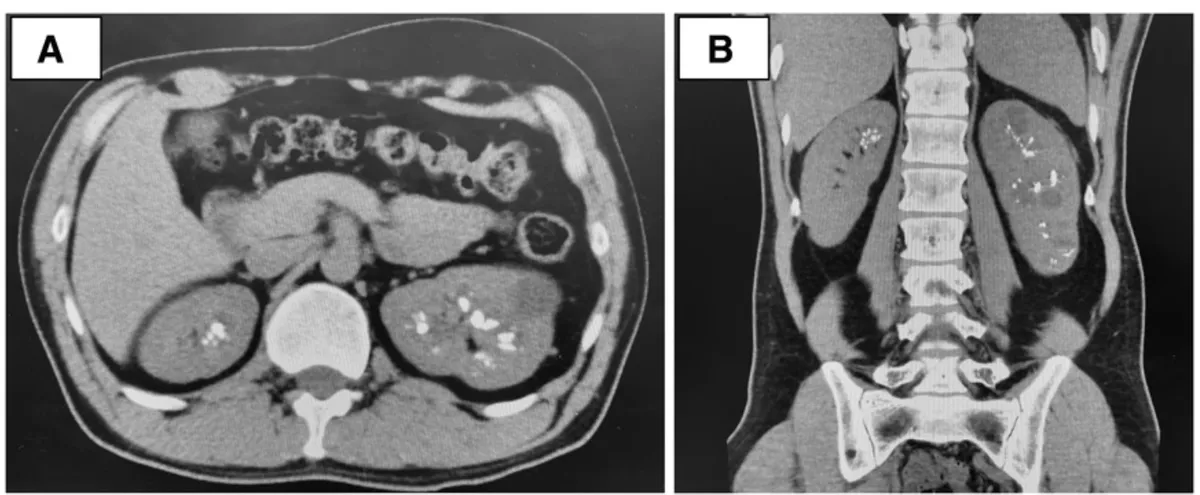

Hematúria e anormalidades em tomografia